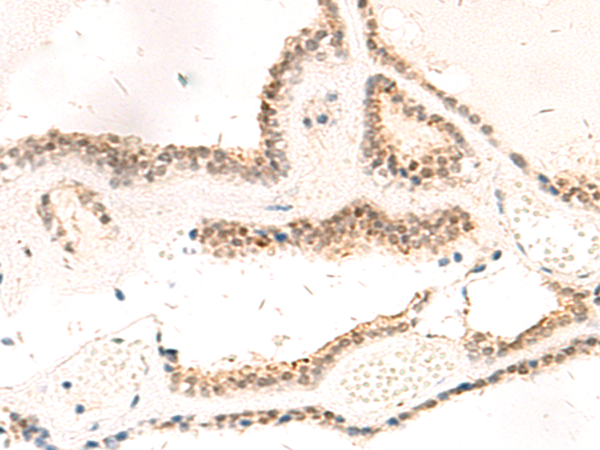

分类: 科研抗体货号: P10047别名: RAB1; YPT1应用: IHC反应种属: Human, Mouse, Rat